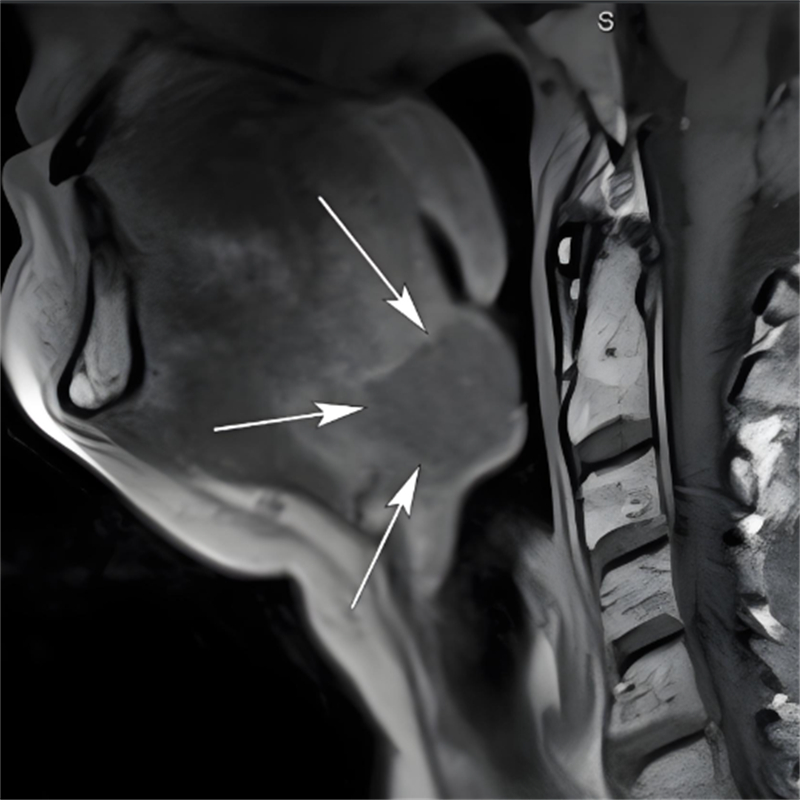

在柳州市人民医院耳鼻咽喉-头颈外科,接诊的田芳云副主任医师在细致查体时发现了关键线索:当轻压患儿舌体,舌根部竟显露一个半球形囊性肿物。结合详尽的病史询问,田医生高度怀疑患儿罹患的是“先天性舌内型甲状舌管囊肿(舌甲状舌管囊肿)”。

这一诊断让所有人都紧张起来。舌甲状舌管囊肿,位于舌根深部,会阻塞气道,严重时可导致患儿在睡眠中突发窒息,后果不堪设想。

医生介绍,甲状舌管囊肿是颈部较常见的先天性疾病,源于胚胎期甲状舌管未完全闭锁、上皮残留。根据发生部位可分为“舌骨上区型、舌内型、甲状舌骨间隙型、胸骨上区型”四种类型,其中舌内型(舌甲状舌管囊肿)仅占所有病例的0.5-3%。其病灶深藏于舌根内部,位置极其隐秘,临床症状不典型,很容易被漏诊或误诊。